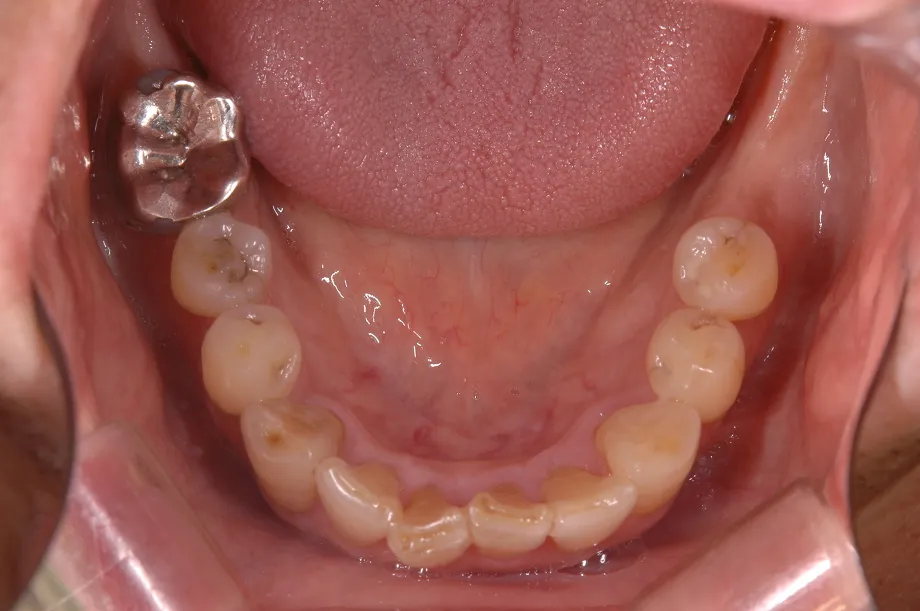

【術前】

【術後】